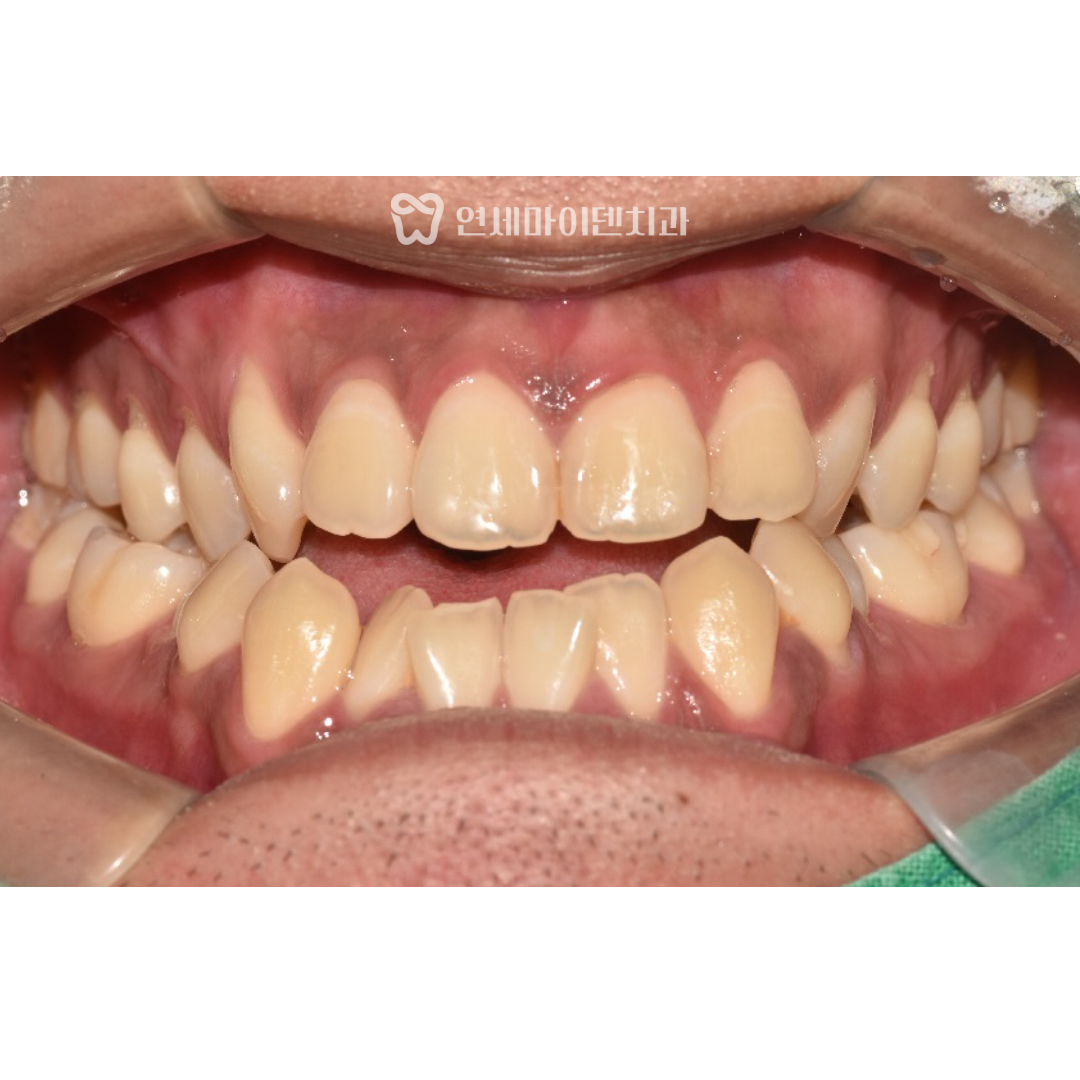

치료 전 사진을 보면, 오른쪽으로 아래턱 틀어짐이 보이고,

윗니와 아랫니의 중심선도 맞지 않았습니다.

턱의 교합이 맞지 않아서 전체적인 치열도 고르지 못한 것을 확인할 수 있습니다.